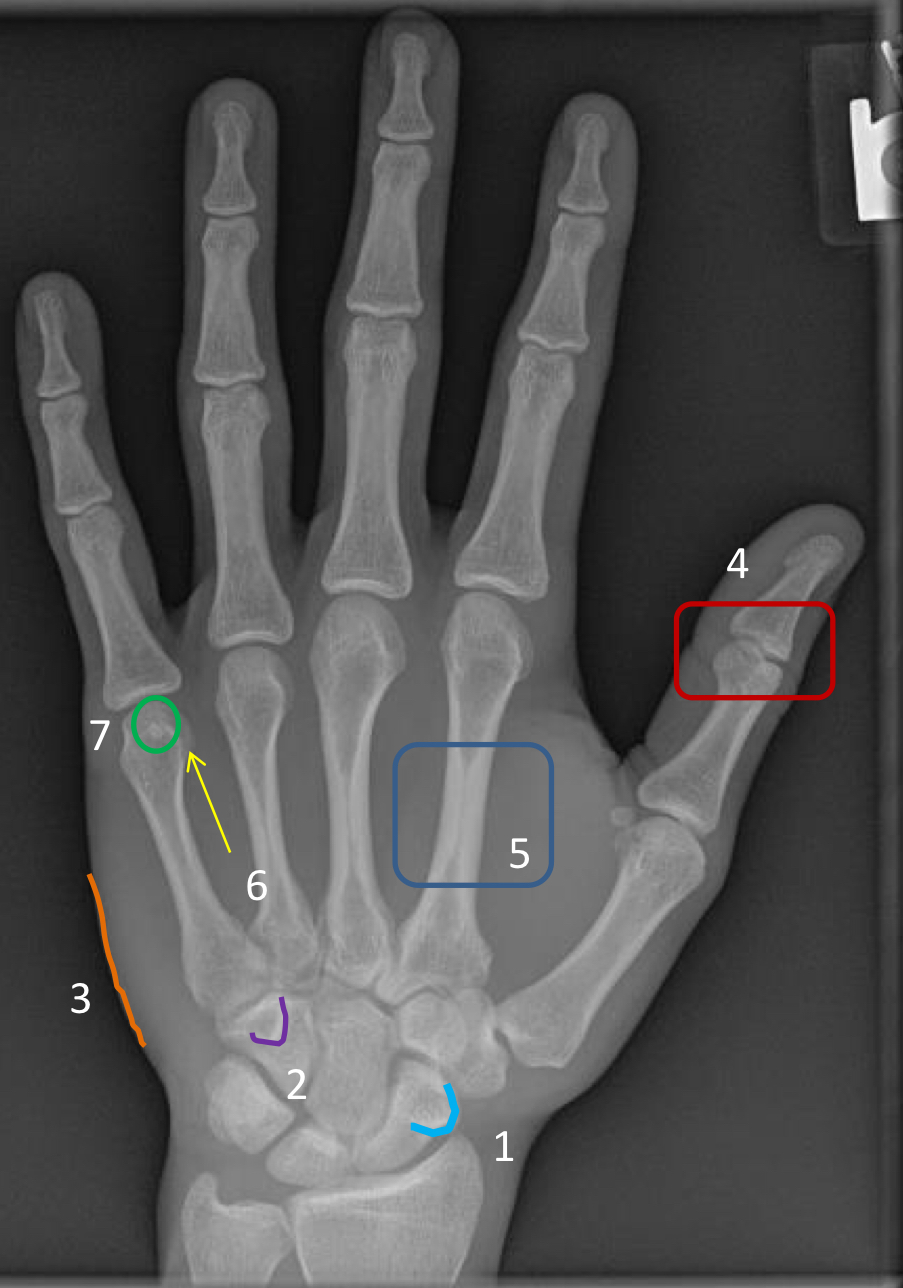

What view is this?

PA hand

purple arrow?

ungual tuft

1?

distal interphalangeal joint of the 2nd digit

2?

4th proximal interphalangeal joint

3?

head of 3rd metacarpal

4?

sesamoid of 2nd metacarpophalangeal joint

5?

base of 2nd metacarpal

6?

base of 1st proximal phalanx